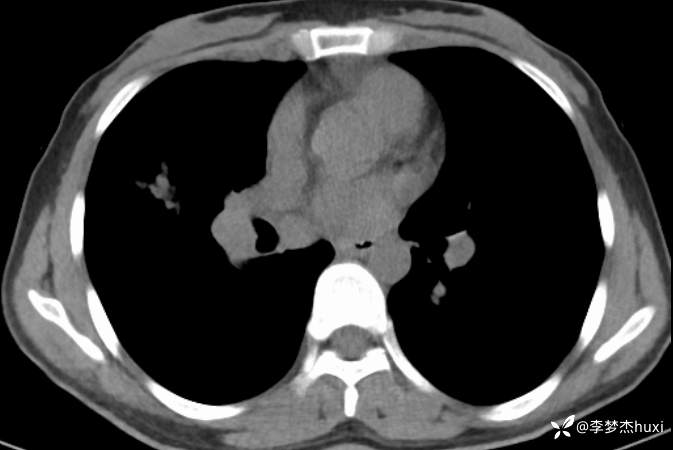

女性35岁,主因咳嗽、咳痰1月,胸部CT报肺炎,猜对乃神医!

女, 35 岁,主因咳嗽、咳痰1月于2025-11-05 08:46入院。

1.现病史:患者中年 女,患者于入院前1月“感冒”后出现咳嗽、咳痰,为黄白痰,不易咳出,无痰中带血,咽部刺痒不适,咳嗽明显,无胸痛,无胸闷、憋气,无恶心,未呕吐,无腹痛、腹泻,无尿频、尿急、尿痛,于院外口服药物(具体不详)治疗,病情未见好转,2025-11-4于我院门诊查胸部CT提示右肺炎症。为进一步诊治来我院;门诊以“肺炎”收入院 。

肺炎。